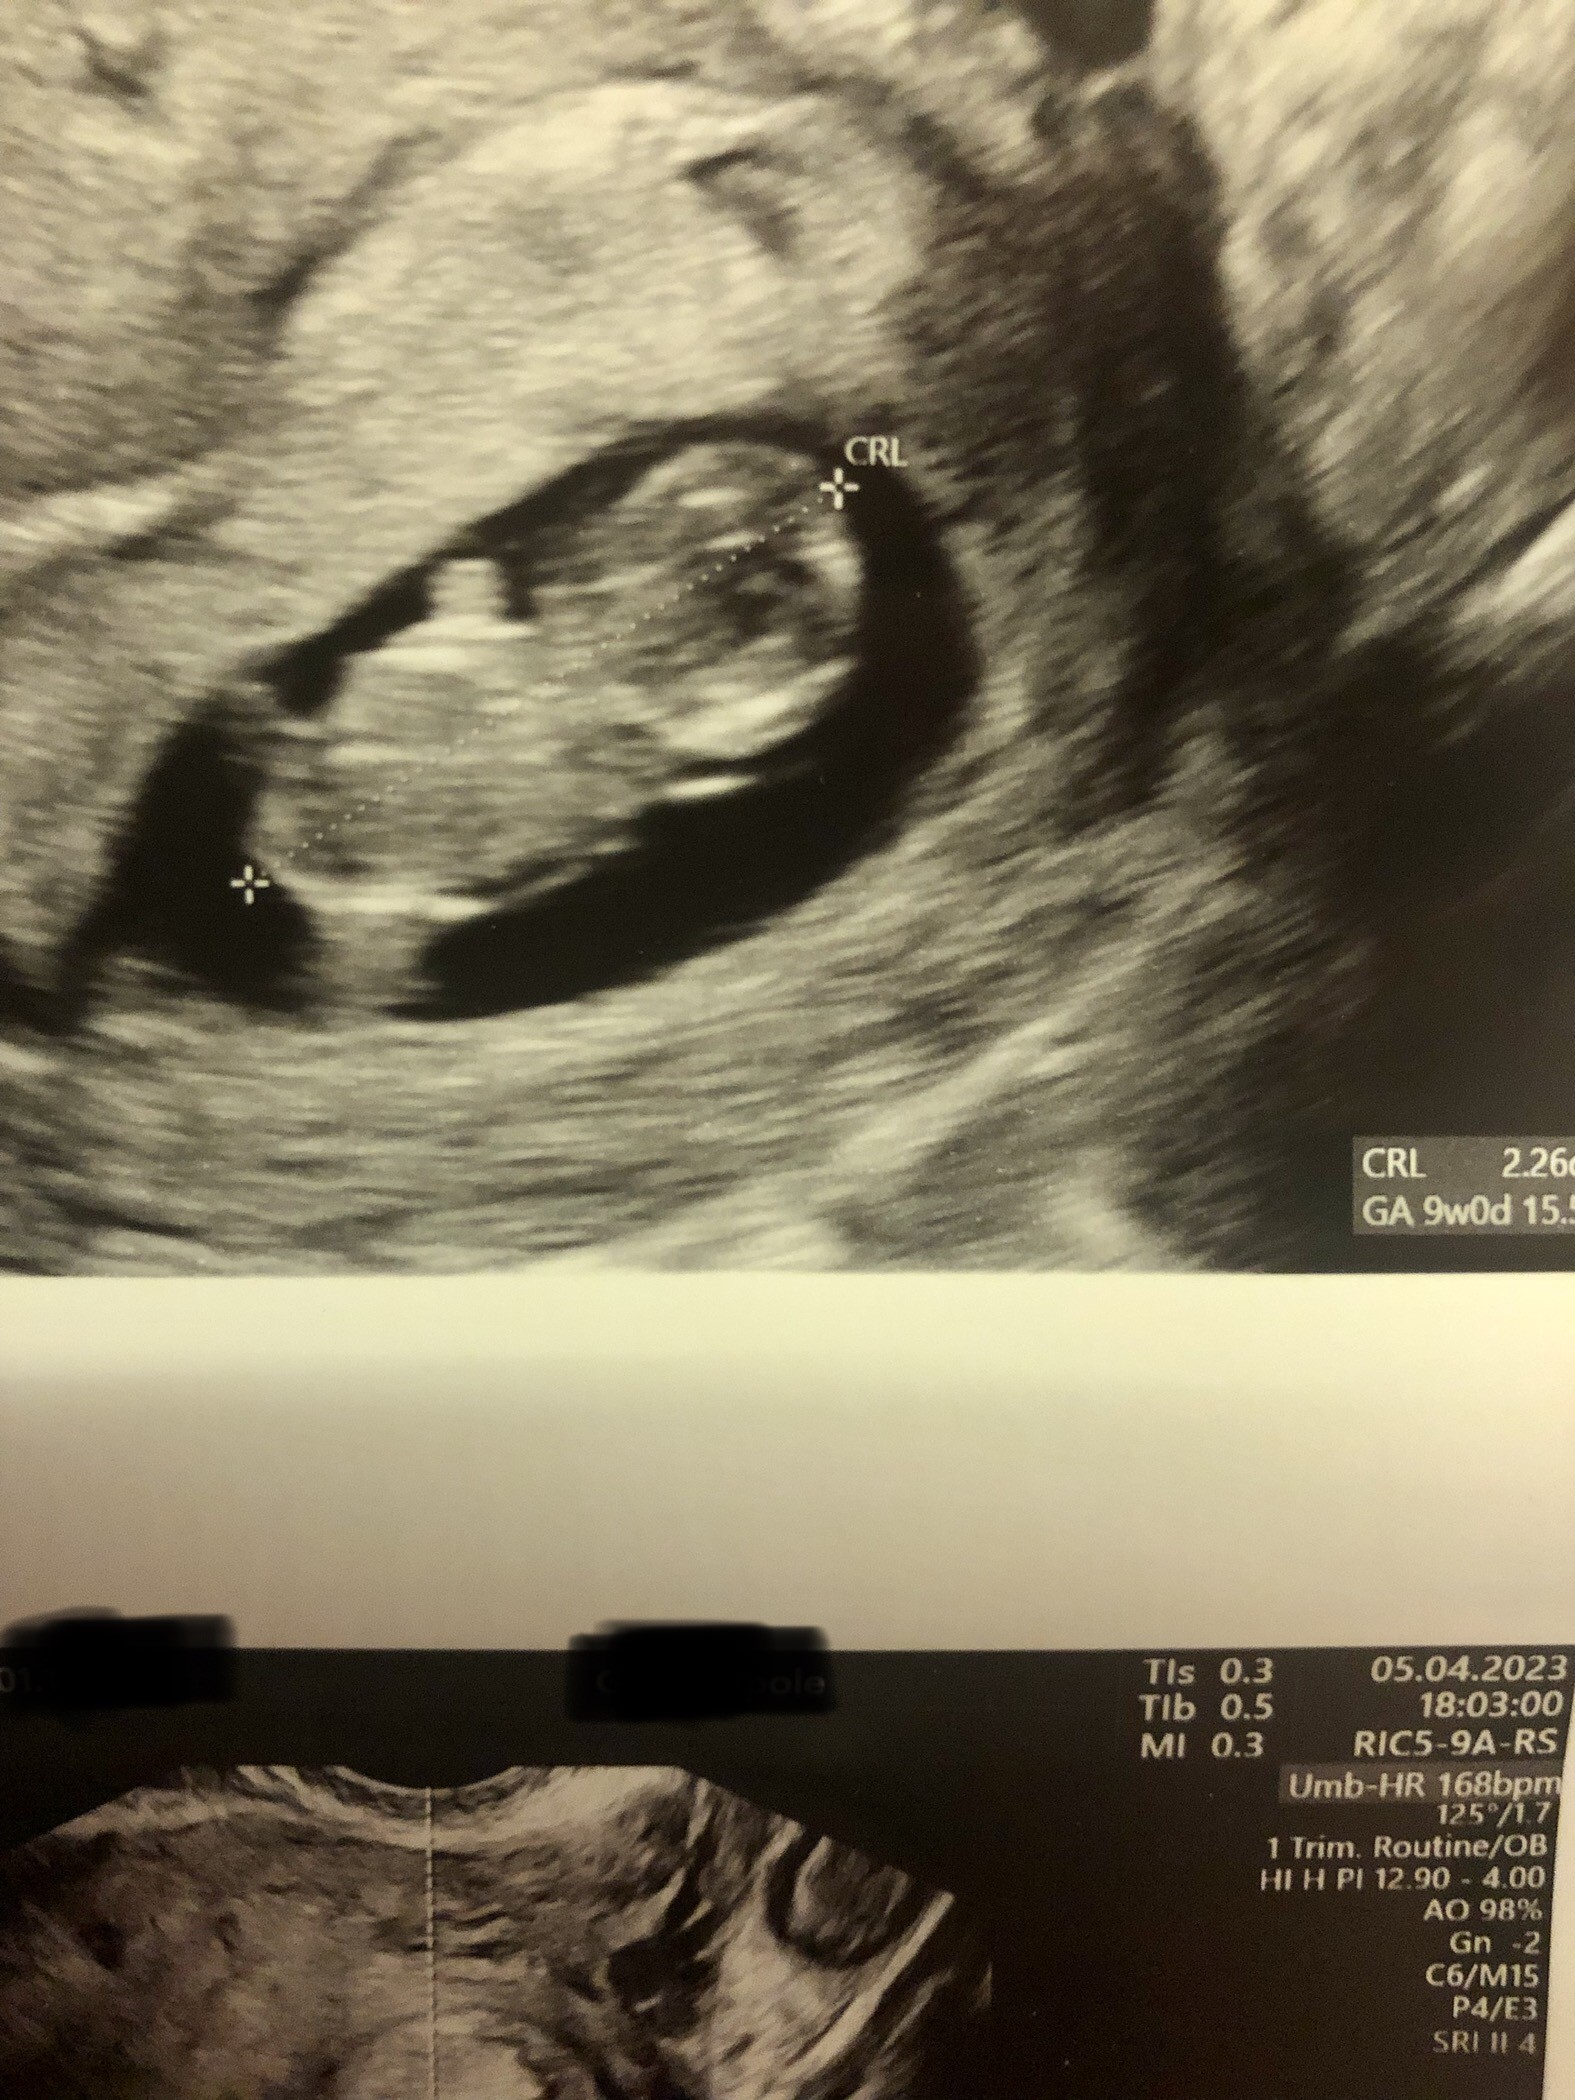

Poza tym u bombelka dobrze, serduszko bije 168 uderzeń/min.